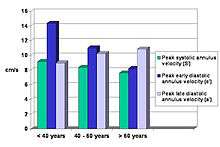

Normal values and physiology

Normal gender and age related reference values For both S', e' and a' ahave been established in the large HUNT study, comprising 1266 subjects free of heart disease, hypertension and diabetes.[26]

This study also shows that both S' and e' values decline with age, while a' increases (fig). There is also a significant correlation between S' and e', also in healthy subjech, showing the connection between systolic and distolic function.

The e'/a' ratio becomes <1 about 60 years of age, which is similar to the E/A ratio of mitral flow. Women has slightly higher S' and e' velocities than men, although the difference disappears with age. The study also did show that velocities were highest in the lateral wall, and lowest in the septum. The E/e' was thus dependent on the site of e' measurement. The ratio was also age dependent.